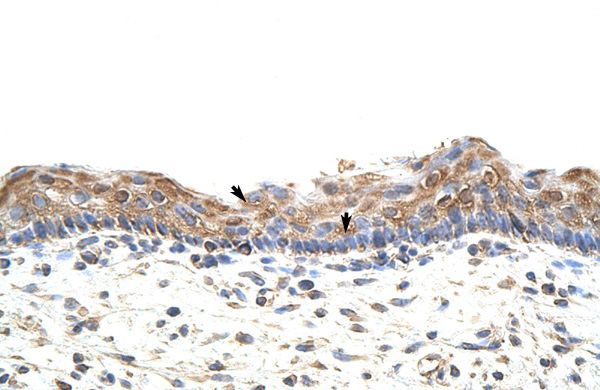

IHC-P analysis of human skin tissue using GTX47168 GNB1L antibody at 4-8μg/ml.